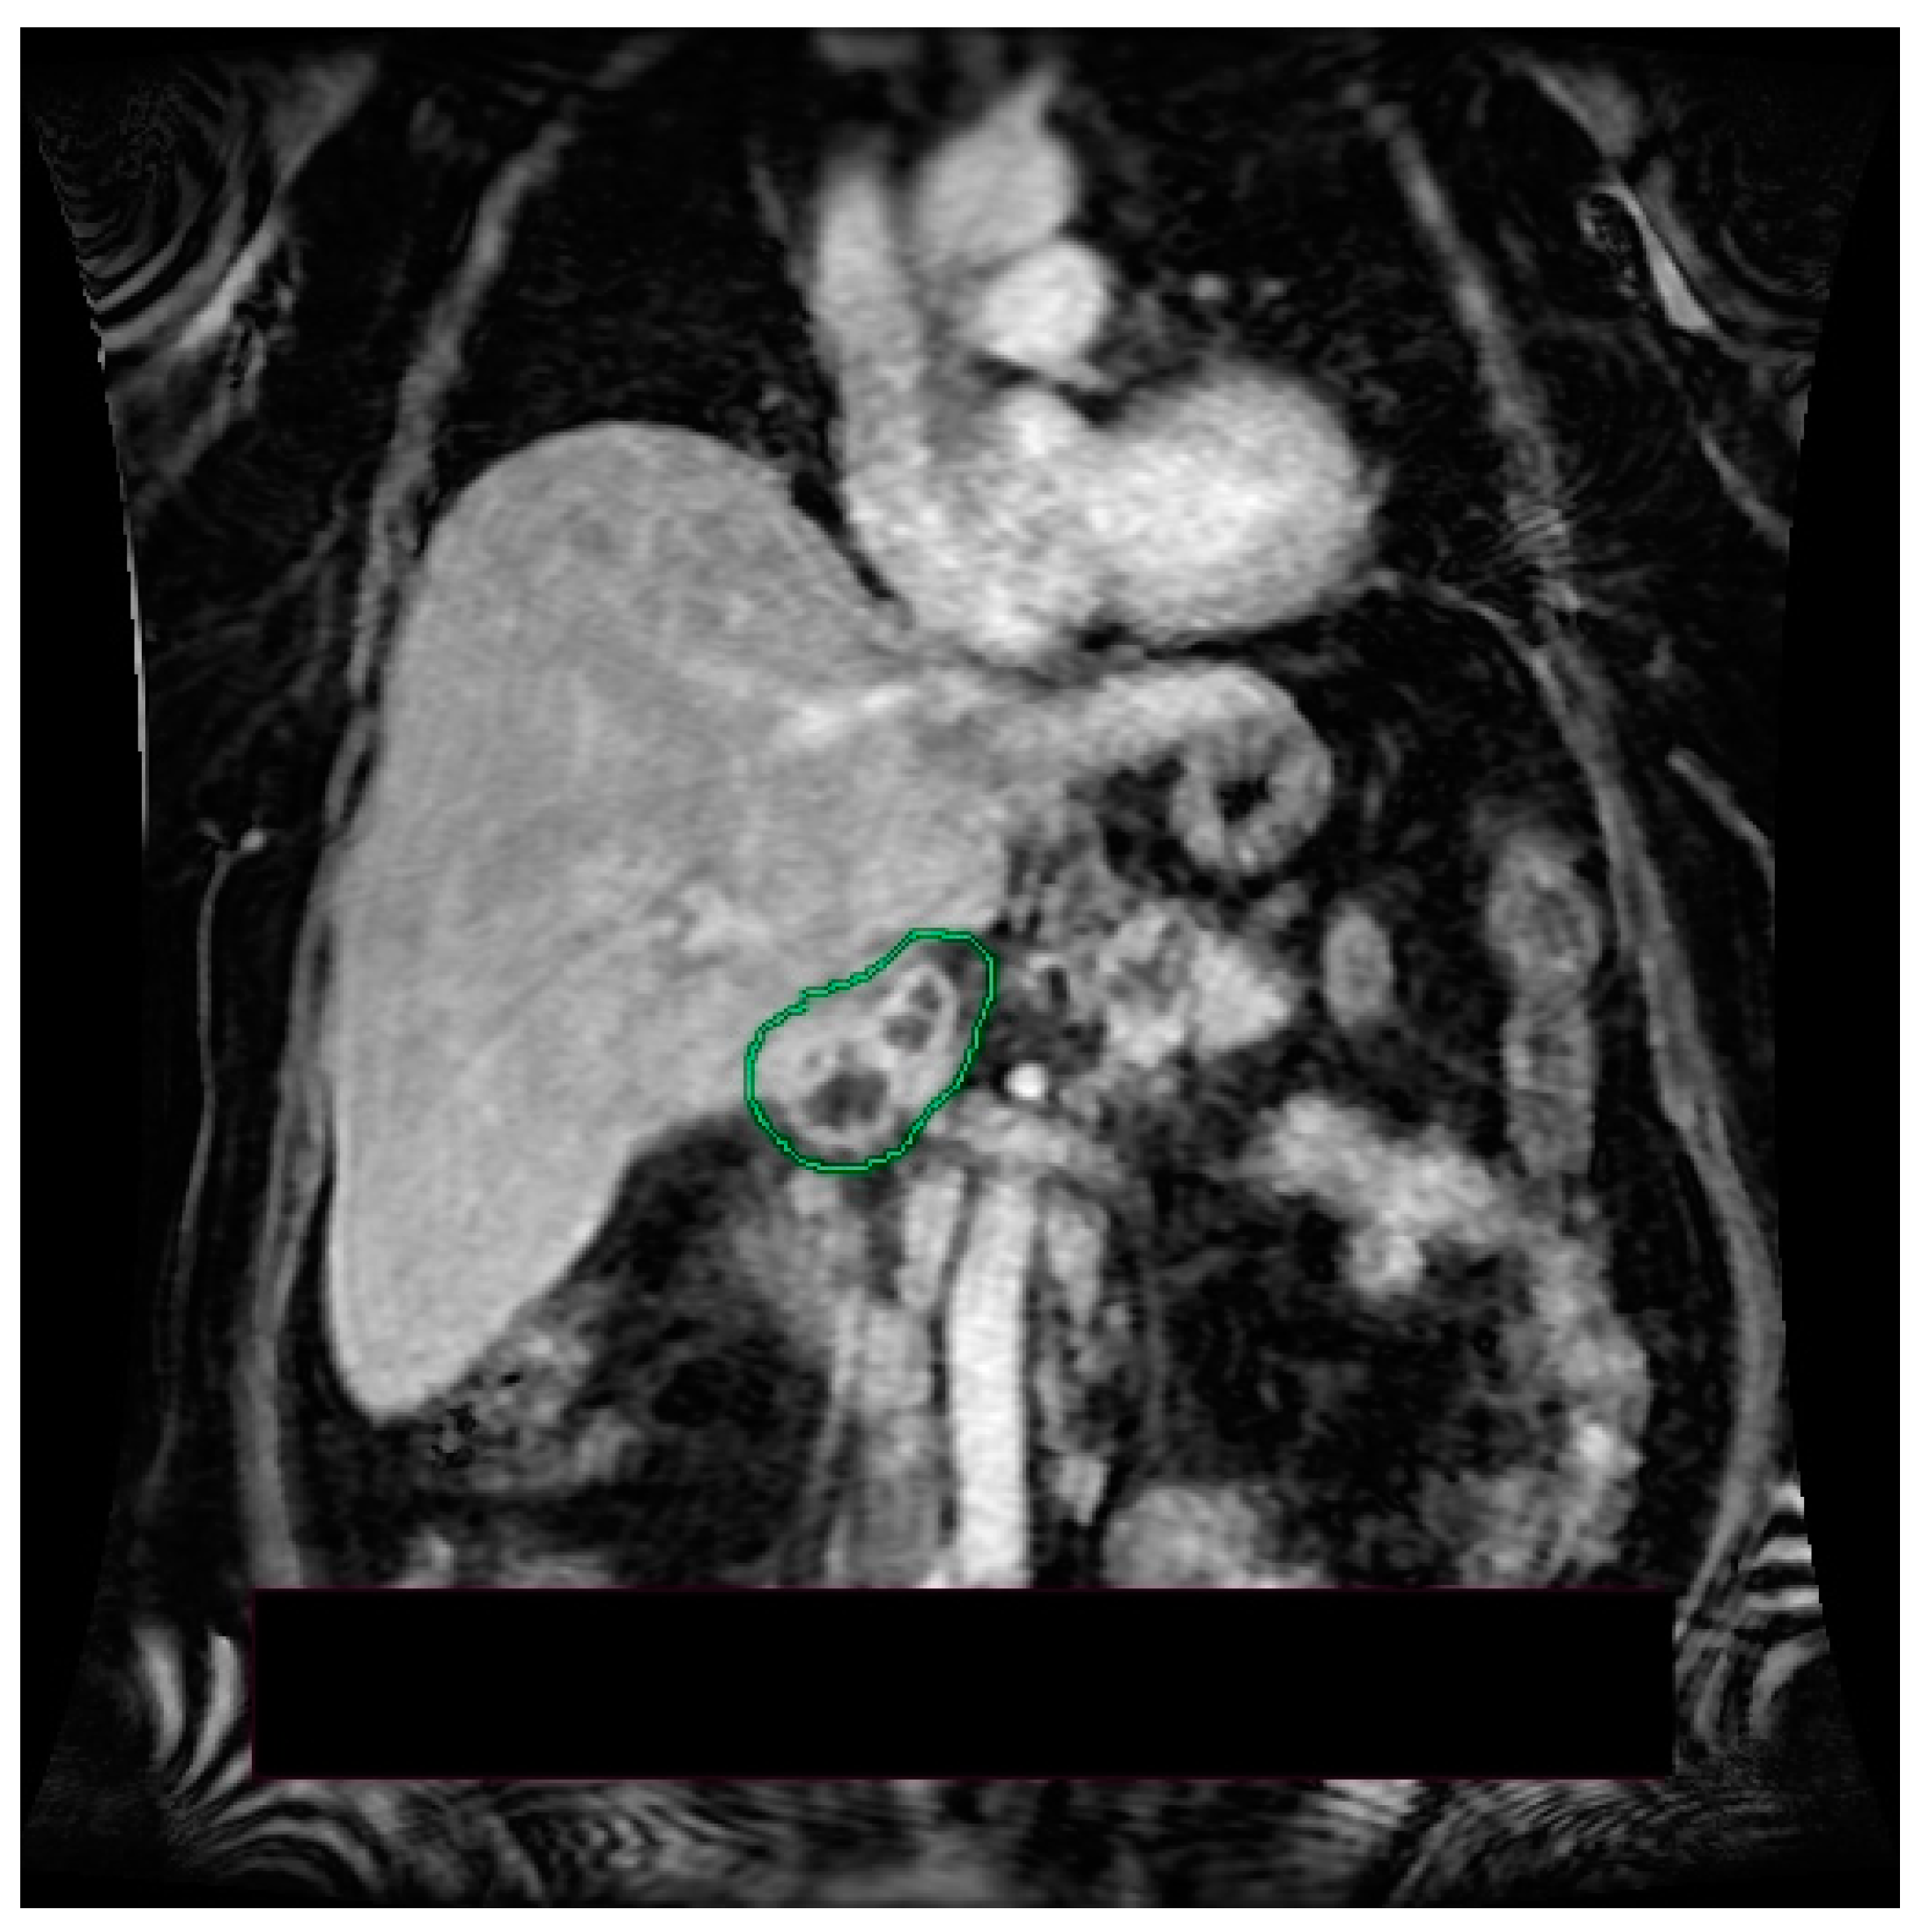

2. Case Presentation